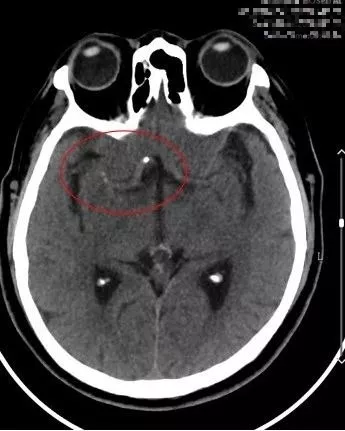

9:40分左右,患者逐渐开始出现烦躁、嗜睡,查体:言语不清,左侧肢体肌力0-1级,急查头颅MRI+MRA+颈部MRA阅片见,右侧基底节区急性脑梗死,右侧大脑中动脉闭塞。

复查头颅CT(09:48分)

头颅MRI+MRA(08-03日 11:50左右)

患者症状逐渐加重,头颅MRA示右侧大脑中动脉闭塞,是本次病灶责任血管,目前患者在取栓时间窗内,有行桥接动脉机械取栓指征。与患者家属沟通后全麻下行右侧大脑中动脉取栓术。手术风险及相关注意事项向患者家属告知。